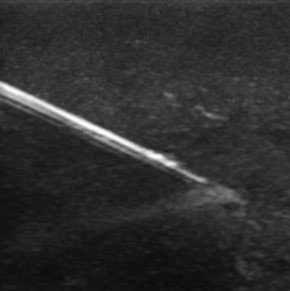

Vascular Occlusion prevention is the future of safety within dermal filler injections. Although dermal filler can be dissolved with Hyalase – Hyaluronidaise. It would be better to never have this possibility occur in the first place. Prevention is always better than cure. The number one fear that puts people off having dermal filler treatments done is the potential of vascular occlusion. If this can be avoided by utilising ultrasound technology then this opens up a whole new potential for customers or patients.

We have been working blindly for many years. And now we can confidently train you to be able to fully map out the face in terms of arteries and much more. We can measure depths of arteries and diameters and much much more.

The ability to offer ultrasound guided injections is going to be one of the only true ways to separate yourself from almost every other aesthetic practitioner in the country. At most there are currently a very small handful. If anyone. Offering this currently. The ability to not only have ultrasound guided injections but also the ability to very quickly and accurately diagnose problems is an extreme advantage.In addition to this the ability to see inside someones tissue space and say confidently how much filler is remaining and where exactly it is is a true game changer.

Our course is a fully comprehensive course that not only provides you with the only ultra high frequency portable ultrasound in the world but also teaches you exactly how to use it to its best effectiveness. Over this two day course. You will cover off complications to the very highest level. Along with the most in depth anatomy training available anywhere.